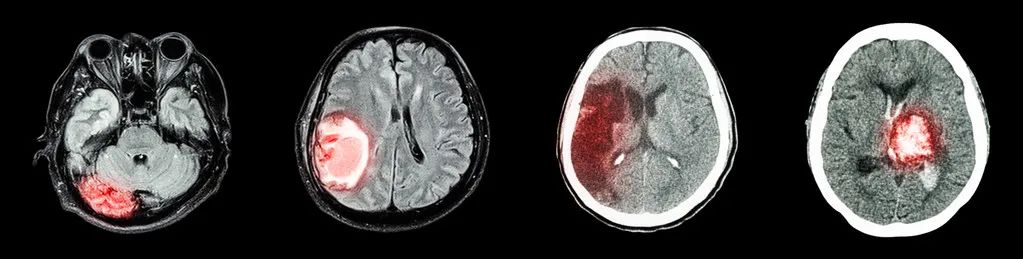

老百姓混淆了中医的中风和西医的中风的概念。西医是这样定义的:脑卒中是脑中风的学名,是一种突然起病的脑血液循环障碍性疾病。又叫脑血管意外。

是指在脑血管疾病的病人,因各种诱发因素引起脑内动脉狭窄,闭塞或破裂,而造成急性脑血液循环障碍,临床上表现为一次性或永久性脑功能障碍的症状和体征,脑卒中分为缺血性脑卒中和出血性脑卒中。中医定义中风分外风和内风,外风因感受外邪所致;内风属内伤病症,即脑卒中。